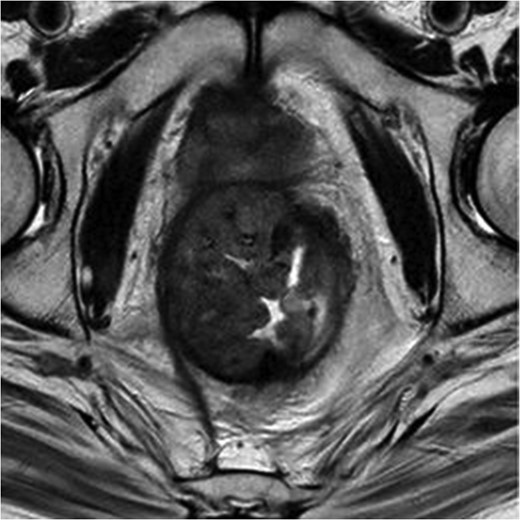

MRI pelvis large field T2 sagittal image through penile shaft showing the lesion involving the corpora cavernosum with extension in the spongiosum.

It is still a controversial subject the reason why the penis, despite its vascularization is a rare site for metastasis. It has been postulated that the route of metastasis include retrograde venous or lymphatic spread, local direct extension, arterial embolism or instrumental spread [1, 2, 4]. Currently the most accepted theory is the mechanism that involves retrograde venous spread from pudendal to the dorsal venous system of the penis [2, 4]. The most common type of presentation is malignant priapism followed by urinary retention, penile nodules, ulceration, perineal pain, oedema, infiltrative enlargement, dysuria and haematuria, with the corpora cavernosa being the most common site of metastasis and the glans and corpus spongiosum infrequently involved [1]. Our case respected the above mentioned cavernosal involvement but also had mild extension into the corpus spongiosum, more to the fact that this isolated metastatic penile neoplasm is extremely rare.